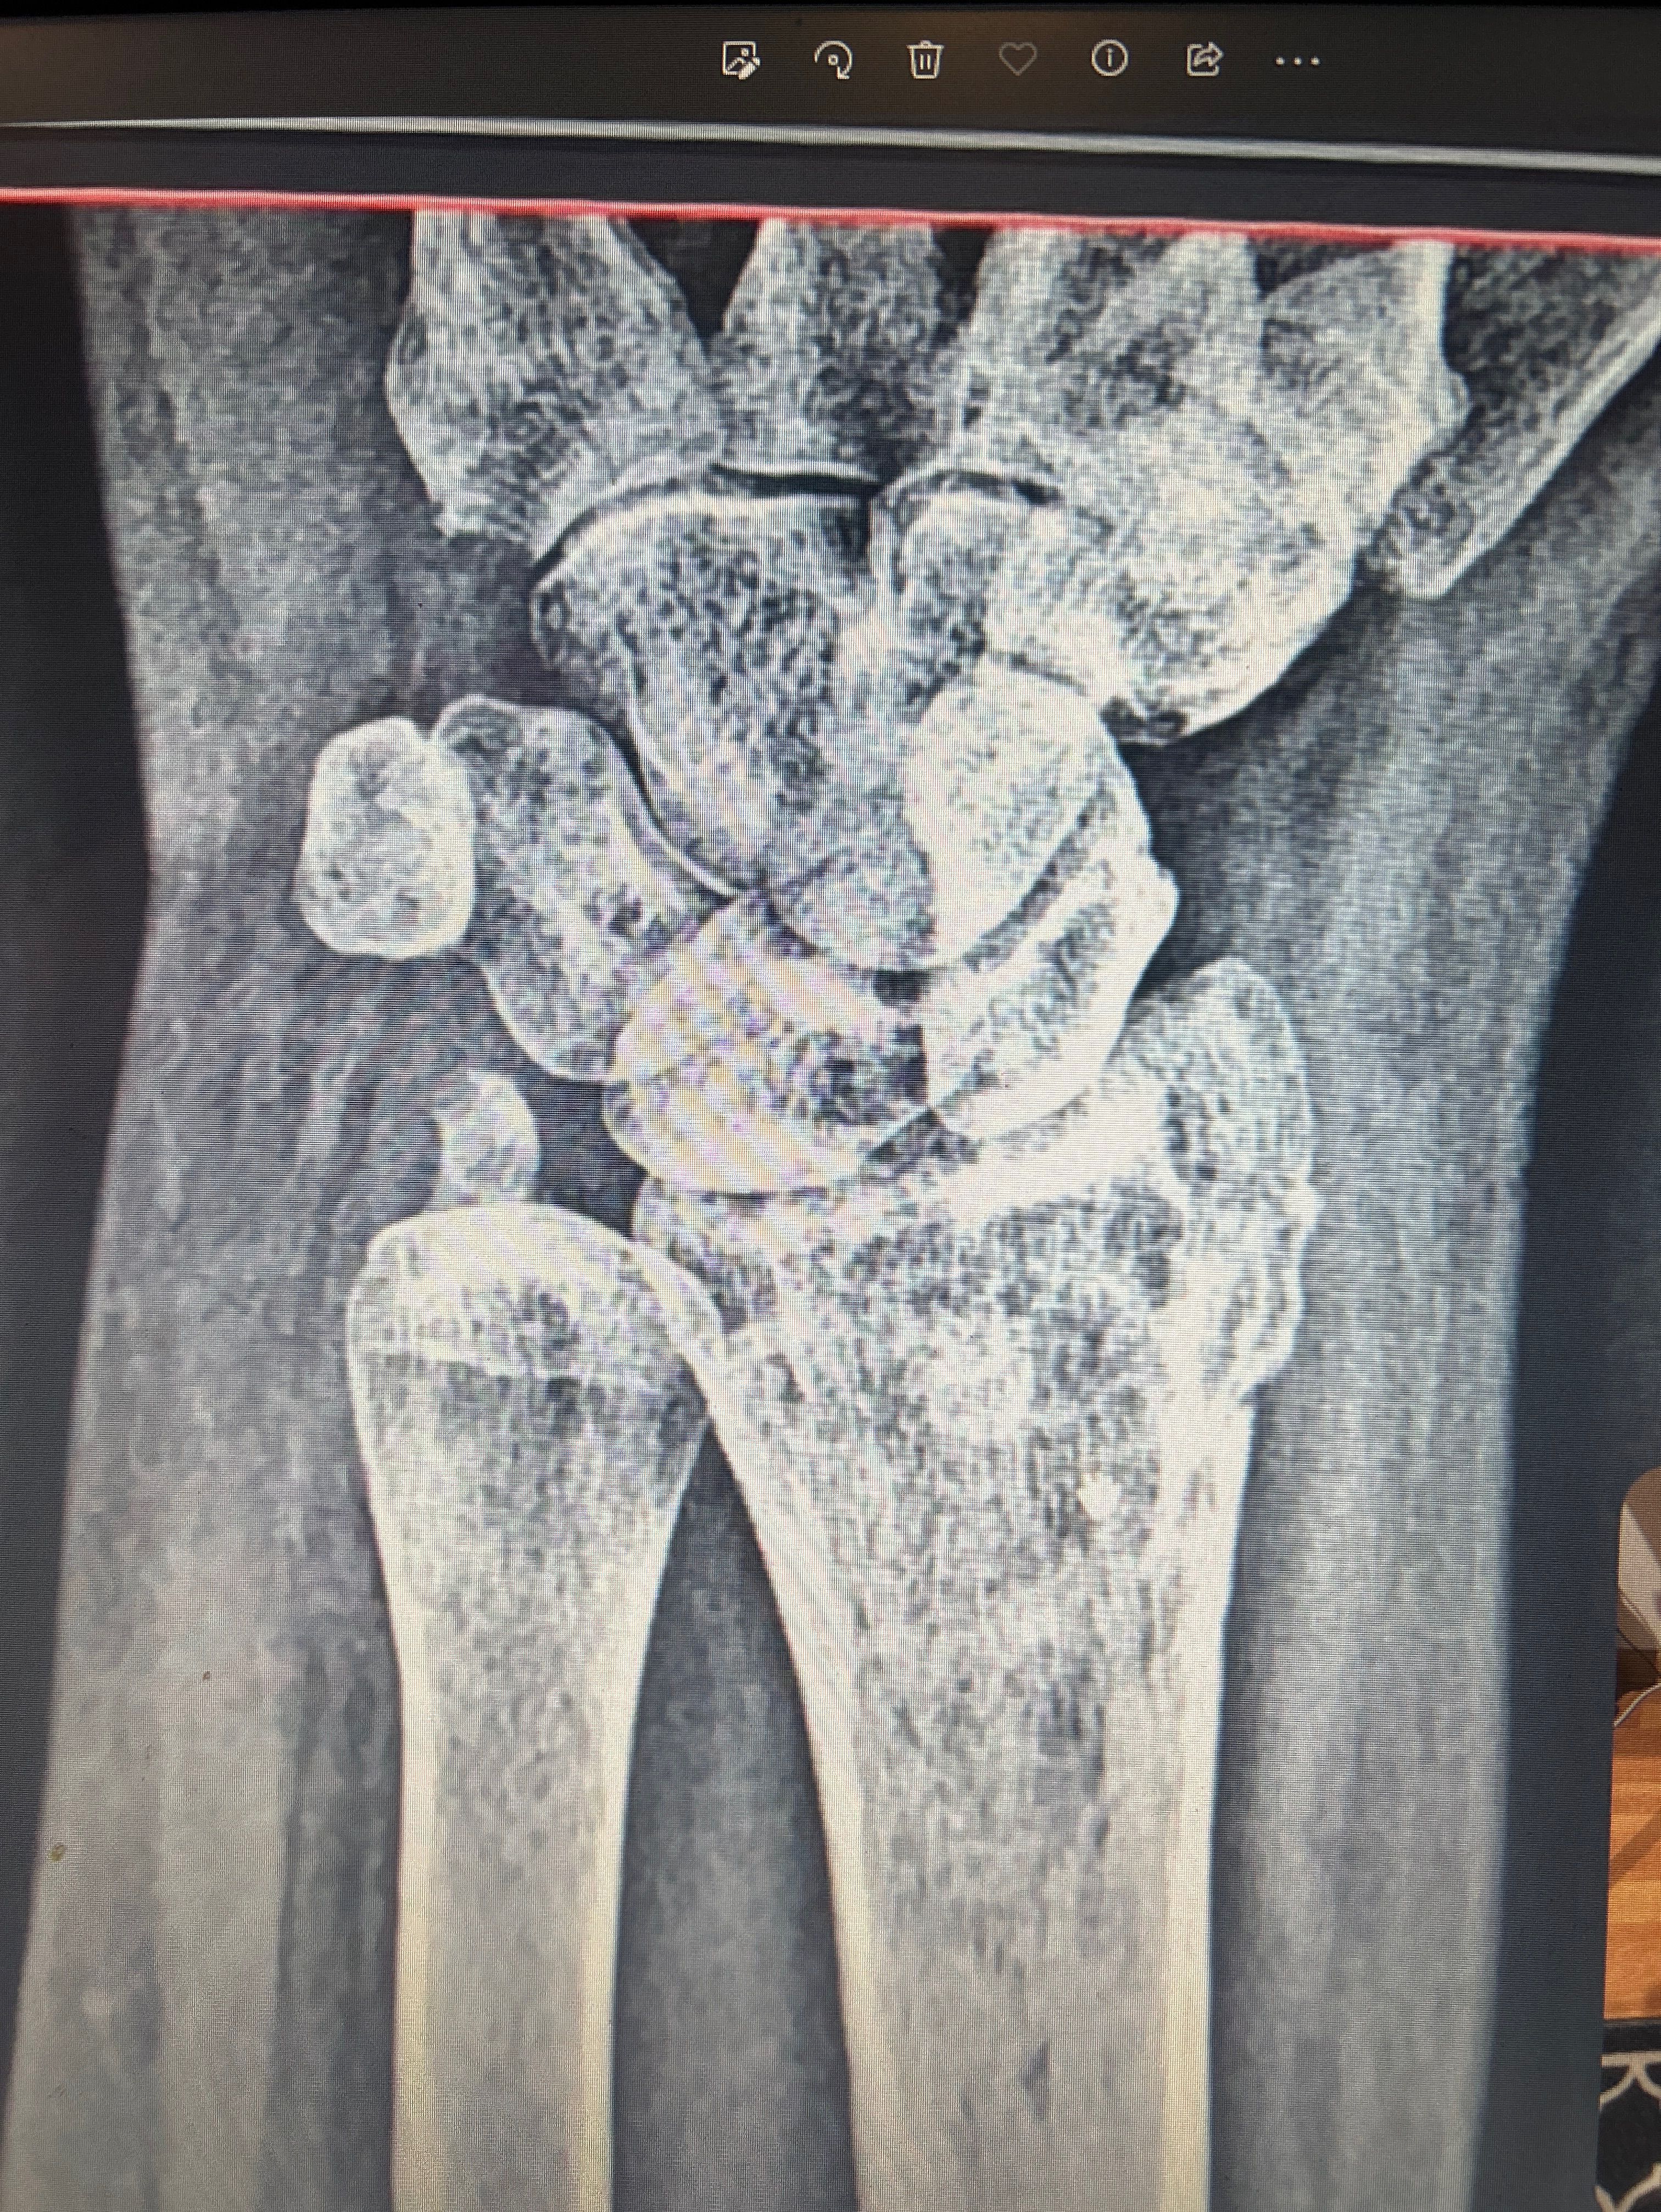

Wrist

2 month ago there was a fracture of the radius , is everything is alright?

Fracture

Healing